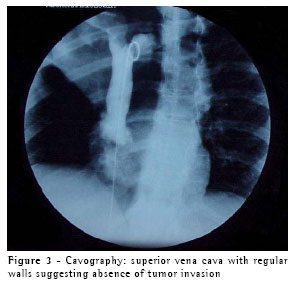

A computed tomography scan of the chest revealed atelectasis of the right

upper lobe (caused by occlusion of the upper lobe bronchus) that extended up to the juxtacarinal portion of the main bronchus, accompanied by infiltration of the wall of the main left bronchus, which resulted in invasion of the right branch of the pulmonary artery and of the arch of the azygos vein. There was no sign of invasion of the chest wall or of pleural effusion (Figure 2). Tomographic findings led us to suspect invasion of the superior vena cava and azygos vein. Therefore, we performed a cavography, which did not reveal any involvement of these structures (Figure 3).